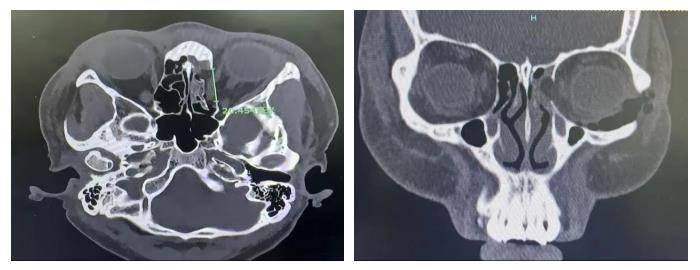

情况紧急!医院立即启动创伤中心与眼科急诊联合救治机制。从患者入院登记开始,绿色流程同步启动:急诊医学科快速完成生命体征评估、伤口初步处理;影像科开通“急诊通道”,15分钟内完成眼眶CT检查并出具报告,明确“左眼侧眼眶内侧壁、下壁骨折,眼外肌嵌顿”的诊断;眼科团队第一时间介入,确定急诊手术方案。